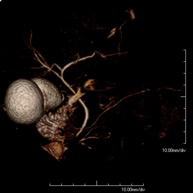

- Abdominal aorta MRI angiography

A non-invasive diagnostic test that involves studying the abdominal aorta, obtaining high-definition anatomical images using an electromagnetic field and radio waves (with transmitter and receiver). The use of paramagnetic contrast (gadolinium) is essential. However, it is a radiation-free procedure. The quality of the images allows for 2D and 3D reconstructions. It is indicated in patients with vascular disease (atherosclerosis), aneurysm studies, pre-surgical studies of lesions adjacent to the abdominal aorta as a vascular ‘map’, etc.

- Aortic-iliac MRI angiography

A non-invasive diagnostic test that involves studying the abdominal aorta and iliac arteries, obtaining high-definition anatomical images using an electromagnetic field and radio waves (with transmitter and receiver). The use of paramagnetic contrast (gadolinium) is essential. However, it is a radiation-free procedure. The quality of the images allows for 2D and 3D reconstructions. This test is particularly recommended as a pre-surgical study (vascular map) prior to percutaneous or surgical interventions on the abdominal aorta and iliac arteries, as a complementary study in patients with lower limb ischaemia, etc.